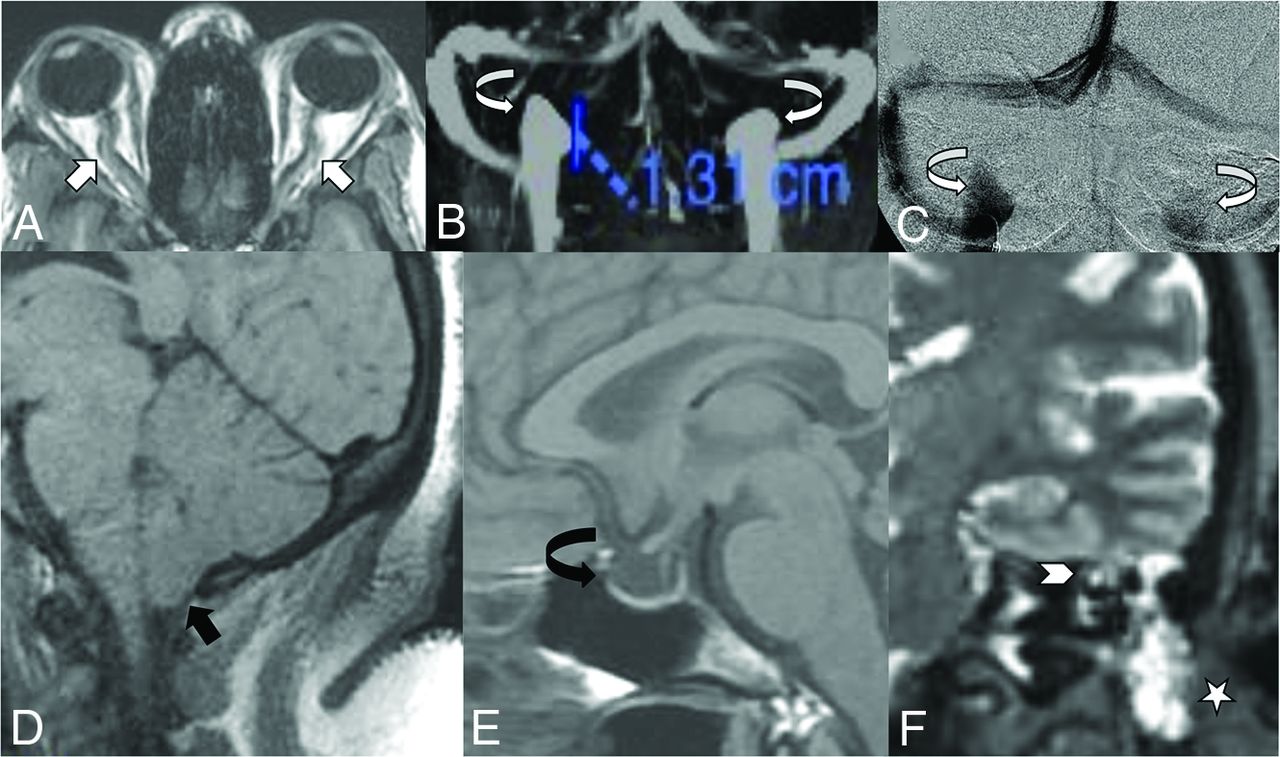

All venous sinus stenoses included were considered severe at the time of initial and retrospective study review. The location and type of stenosis were recorded on the basis of findings made from MRV examinations. However, because all cohort patients underwent venous sinus stent placement, conventional venography images were available for review and useful in corroborating the stenosis subtype characterized on MRV. Stenosis lengths were not recorded. Stenosis caused by intraluminal processes such as prominent arachnoid granulations were classified as intrinsic stenosis. Stenosis caused by compression of the venous sinus from brain parenchyma against the adjacent calvaria was classified as extrinsic stenosis. In the event of intrinsic stenoses preceding segments of extrinsic stenosis, the overall stenosis was still categorized as extrinsic stenosis. The presence of poststenotic dilation of the lateral sinus was classified as “fusiform” if it had the appearance of a shallow, wide-neck aneurysm with a 25%–50% increase in size relative to its expected diameter. The term “saccular” was used if it had the appearance of a discrete dome with the depth larger than the neck dimensions. Examples of these findings are shown in Fig 1.

A, Axial postcontrast MRV demonstrating extrinsic stenosis from the overlying cerebellum (short white arrow). B, Contrast-enhanced 3D-MRV image shows poststenotic sigmoid sinus enlargement (curved white arrow). C, Accompanying lateral venography confirms stenosis (white arrow) and sinus enlargement (curved white arrow) seen on the corresponding MRV. D, Separate axial postcontrast MRV shows intrinsic stenosis from arachnoid granulations (black arrow). E, A coronal postcontrast MRV sequence shows lateral sinus dehiscence with a venous aneurysm (curved black arrow). F, Accompanying frontal venography confirms stenosis (short black arrow) and a saccular aneurysm (curved black arrow) seen on the corresponding MRV.